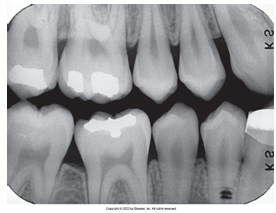

What is the problem with this OVERDEVELOPED FILM X-ray?

Appears dark, Excessive developing time, Developer solution too hot, Inaccurate timer or thermometer, Concentrated developer solution

How would you resolve this OVERDEVELOPED FILM X-ray?

Check development time • Check developer temperature • Replace faulty timer or thermometer • Replenish developer with fresh solutions as needed